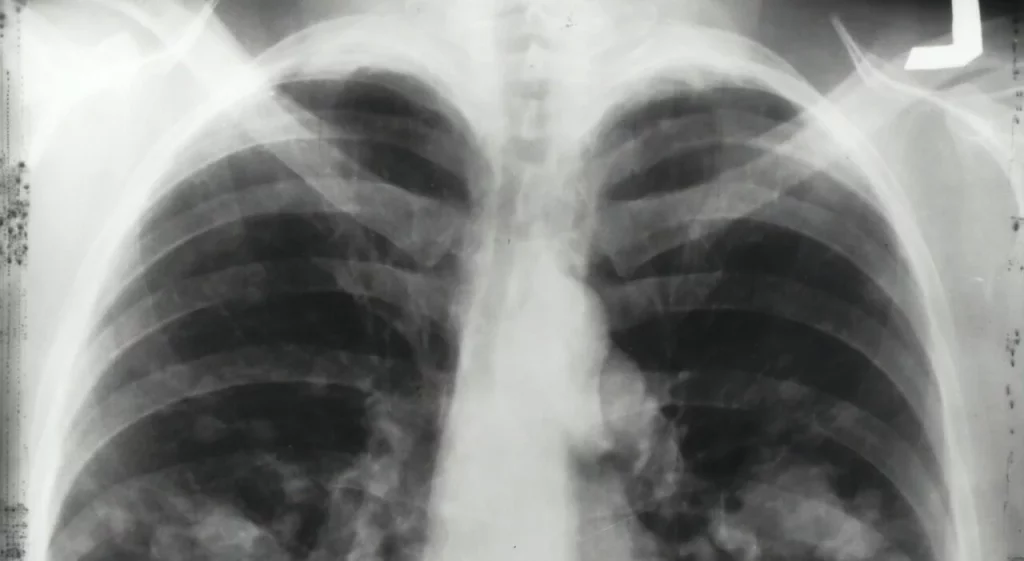

Il tumore al polmone è una delle principali cause di mortalità nel mondo, ma è importante notare che non colpisce solo coloro che hanno una lunga storia di fumo. In molti casi, individui giovani e in salute sono colpiti, portando a una crescente necessità di trattamenti più specifici e meno invasivi. Secondo i dati dell’Organizzazione Mondiale della Sanità (OMS), il 20% dei casi di cancro ai polmoni si verifica in non fumatori, una statistica che ha spinto i ricercatori a cercare nuovi approcci terapeutici.

Le forme rare di tumore al polmone possono manifestarsi in modi peculiari e spesso richiedono un’attenzione diagnostica e terapeutica specifica. Molti pazienti possono inizialmente confondere i sintomi con condizioni meno gravi, ritardando di fatto la diagnosi e aumentando il rischio di complicazioni. I sintomi includono tosse persistente, affaticamento, e perdita di peso improvvisa.